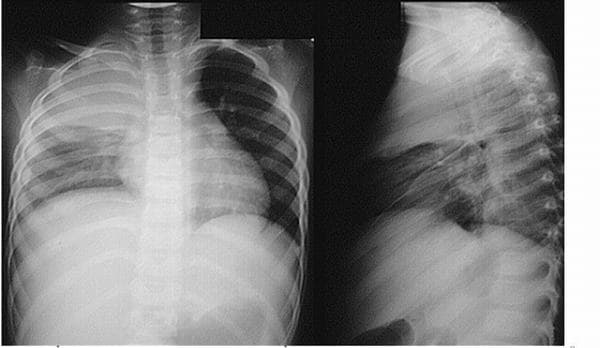

Trước khi đưa ra phương pháp phù hợp để điều trị tràn dịch màng phổi, bác sĩ cần thăm khám và chỉ định làm các xét nghiệm cụ thể nhằm xác định mức độ chất lỏng tích tụ trong phổi. Các phương pháp chẩn đoán cần được áp dụng là chụp CT hoặc X-quang phổi. Ngoài ra người bệnh có thể cần chọc dò dịch màng phổi để làm xét nghiệm nhằm tìm ra nguyên nhân gây bệnh để có biện pháp điều trị triệt để.